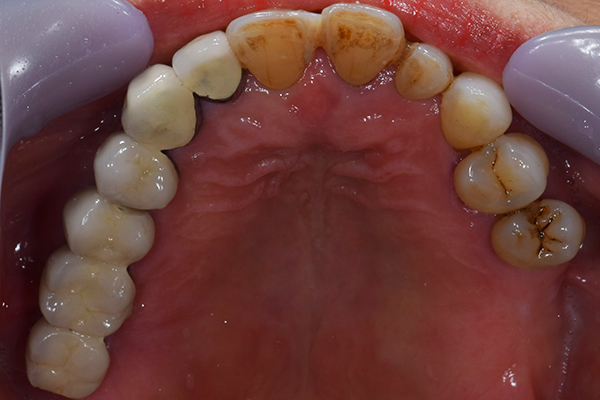

ケース5(金属使用 部分床義歯)

入れ歯をなくしてしまったので、あたらしく作りたい患者様です。

お口に入っている状態です。嘔吐反射が強かったため、うわあごの部分をくり抜いて作っています。

そのためにはしっかり歯に維持力をかける事、歯茎の部分に圧をかけるため、金属をつかって入れ歯を作成しました。

年齢 80代・女性

主訴 入れ歯をなくしたのであたらしくつくりたい。

治療期間 1ヶ月

治療費 義歯:330,000円(税込)

治療方針 以前作った入れ歯は気に入っていたが無くしてしまったとのことで、作り直しました。

上には残っている歯がありますが、入れ歯がない状態が続くと、歯へのダメージが強いことが考えられましたので、急ピッチで作っていくことにしました。

治療内容 入れ歯をつくるための前処置はとくに必要なかったため、すぐに入れ歯を作成していきます。

嘔吐反射が強く、普通の上顎の入れ歯を入れた時の違和感が強いため、口蓋部をくり抜いてつくっていきました。

そのため、歯や粘膜に維持負担を強くかけるため、金属を使用していくことにしました。

患者さんのお話をきいていると、前の入れ歯もそういう入れ歯をつくっていたとのことでした。

特記事項 入れ歯は完成してからがスタートです。入れ歯が歯ぐきにこすれて痛みが出る事が多いです。

今回の様な入れ歯ではそういう事が必ずと言っていいほどでます。

そのため、しっかり痛みをとるために入れ歯を調整して、患者さんに合わせた入れ歯にカスタマイズして完成になります。